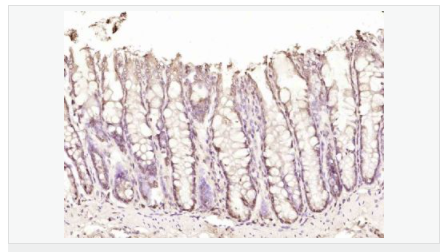

| 产品应用 | ELISA=1:5000-10000 IHC-P=1:100-500 IHC-F=1:100-500 IF=1:100-500 (石蜡切片需做抗原修复) not yet tested in other applications. optimal dilutions/concentrations should be determined by the end user. |